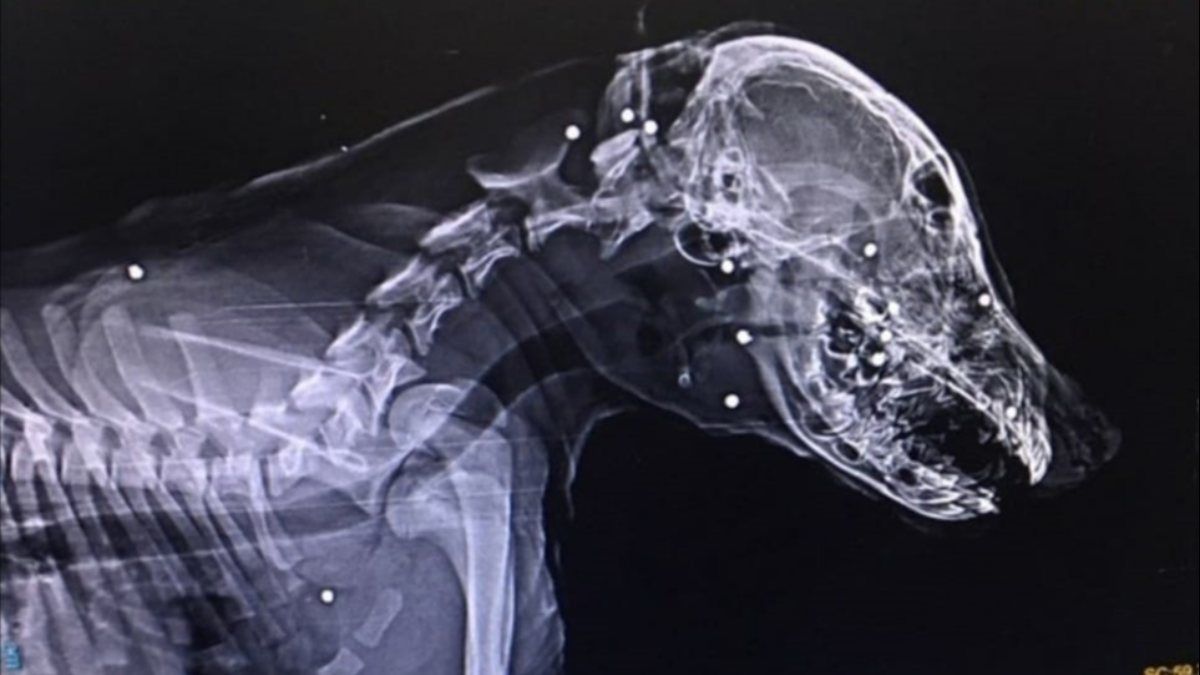

Devrek ilçesinde sahipli bir köpek, kimliği belirsiz kişilerce tüfekle suratından vurularak ağır yaralandı.

Zonguldak'ın Devrek ilçesinde Mert Ekşi’ye ait aylık sahipli köpek, kimliği belirsiz kişi veya kişilerce tüfekle suratından vurularak ağır yaralandı.

Tedavisi için köpeğini aracıyla Zonguldak'a götüren Ekşi’nin köpeğini vuran veya vuranlar için polis, geniş çağlı soruşturma başlattı.